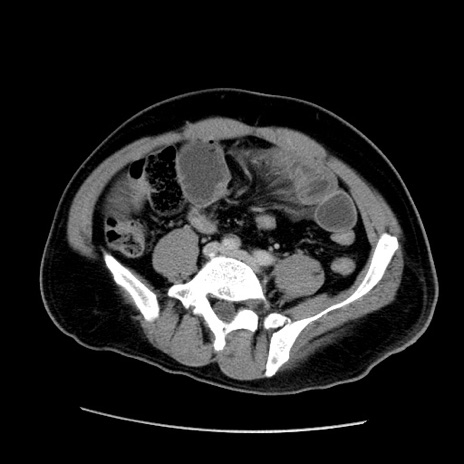

症例22(横断像)

【症例】50歳代男性

【主訴】腹痛

【現病歴】AVMからの被殻出血のため回復期リハ病棟入院中。 本日午後3時頃急に下腹部痛が出現した。

【既往歴】AVM、被殻出血、虫垂炎、高血圧

【身体所見】意識晴明、左半身不全麻痺、会話の理解は良好、36.5°C、腹部:膨隆、全体に板状硬、下腹部正中に圧痛点あり、反跳痛-、筋性防御不明、右下腹部にope scar

【データ】WBC 9400、CRP 0.06